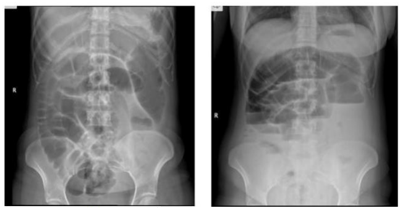

Paciente feminina de 62 anos queixando-se de dor abdominal difusa há 4 dias, em cólicas, associada a distensão abdominal e vômitos fétidos e escuros. Relata que há 4 meses vem apresentando alguns episódios esporádicos de sangramento nas fezes, bem como redução da frequência evacuatória. Nega febre. Nega trauma. Nega cirurgias prévias. Ao exame físico: regular estado geral, descorada, desidratada, anictérica, afebril. Semiologia cardíaca e pulmonar normais. Abdome distendido, com ruídos, doloroso a palpação difusa, sem sinais de irritação peritoneal. Toque retal nota-se lesão ulcerada circunferencial distando 5 centímetros da borda anal. Foras realizadas as radiografias e a tomografia de abdome e pelve abaixo. A conduta mais adequada para este caso é: